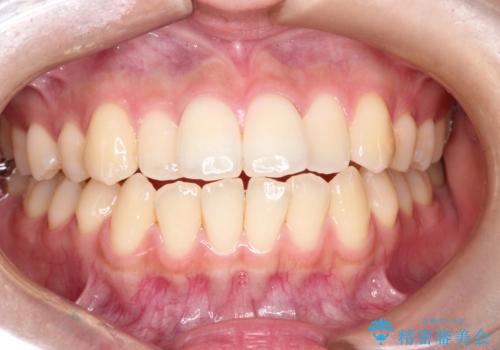

目立たない矯正で口元をすっきりと

担当医 河口智英